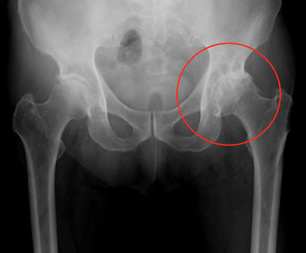

変形性股関節症

変形性股関節症は一次性(加齢や過負荷)と二次性(臼蓋形成不全や先天性股関節脱臼)によるものがあり本邦ではほとんど二次性です。変形性膝関節症よりは発症数は少ないですが関節軟骨の変性・摩耗は同様で骨変形もきたします。まずは投薬、運動療法などの保存療法を行い、症状の軽快が得られない場合は活動量や年齢を考慮して主に前方アプローチ(DAA)にて全人工股関節置換術(図5)を行っています。術後も多くの方が退院まで当院で一貫してリハビリをされています。

図5-1

変形性股関節症

図5-2

全人工股関節置換術後

図5-1

変形性股関節症

図5-2

全人工股関節置換術後